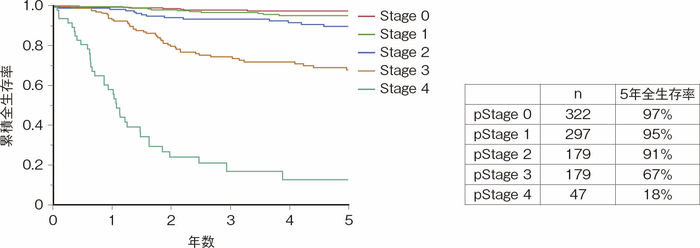

大腸癌研究会で行われたプロジェクト研究「炎症性腸疾患合併消化管癌のデータベース作成と臨床病理学的研究」(以下「プロジェクト研究」)で集積された,UC関連大腸癌症例(1983~2020年)の全生存率を図20に示す。進行度がStage 0, 1, 2のいわゆる「localized」の状態である症例の5年全生存率は90%以上と良好だが,Stage 3の「regional」の症例の5年全生存率は67%と低下してStage 0, 1, 2と比べて有意に不良である1)。遠隔転移を伴うStage 4症例の5年全生存率は18%と非常に不良である。過去に大腸癌研究会の全国登録症例を用いた散発性大腸癌との比較では,Stage 3においてUC関連大腸癌の方が散発性大腸癌よりも予後が悪いことが報告されている(Stage 3の5年生存率はUC関連大腸癌43.3%に対して散発性大腸癌57.4%)2)。両者を直接比較した国内外の報告に関するシステマティックレビューにおける10論文のメタアナリシスは,散発性大腸癌に比べてUC関連大腸癌の全生存率は有意に不良であることが示されている(ハザード比(HR)1.35)3)(CQ 27)。

図20 UC関連大腸癌(全生存率)